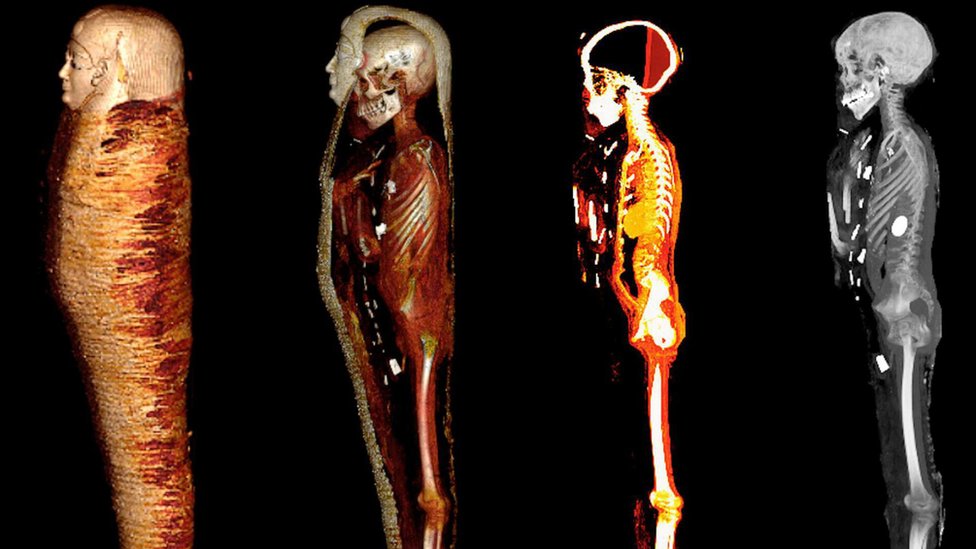

To se promenilo kad je tim predvođen doktorom Saharom Salimom, sa Univerziteta u Kairu, odlučio da prouči mumiju iz pomoć CT skenera.

Snimci su omogućili da se utvrdi da je mladić bio iz više klase, budući da je „imao zdrave zube i kosti, bez dokaza o neuhranjenosti ili bolesti“, i zato što su njegovi posmrtni ostaci bili podvrgnuti „kvalitetnom“ procesu mumifikovanja, koji je podrazumevao odstranjivanje mozga i unutrašnjih organa.

Mumija, za koju se procenjuje da potiče iz poznog Ptolomejskog perioda (332-30. godine p.n.e.), pronađena je u Edfuu, na jugu zemlje, 1916. godine.

Posmrtne ostatke „zlatnog dečaka“ štitila su dva sarkofaga: na spoljnom se nalazio natpis na grčkom, a unutrašnji je bio napravljen od drveta.

Leš je nosio zlatnu masku.

Danas je upotreba kompjuterizovane tomografije postala sjajno oruđe za proučavanje ostataka bez njihovog oštećivanja, što će naučnicima omogućiti da otkriju više o „zdravlju, verovanjima i sposobnostima ljudi iz drevnih vremena“, kaže ovaj stručnjak.

„Kompjuterizovana tomografija predstavlja značajan napredak u radiologiji.

„Umesto da se koristi samo jedan snimak, hiljade projekcija tankih delova (isečaka) tela mogu se kombinovati u potpuni trodimenzionalni model“, zaključuje on.